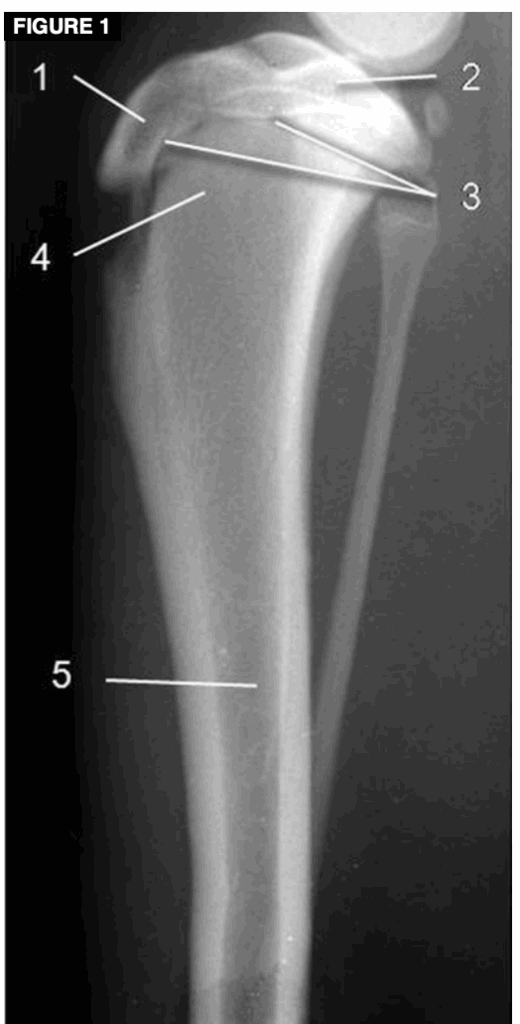

Las placas de crecimiento son estructuras complejas compuestas principalmente de cartílago hialino —un tejido blando y flexible— que gradualmente se transforma en hueso sólido a medida que el cachorro madura. En una radiografía de un cachorro, estas placas se ven como líneas más oscuras entre el extremo del hueso (epífisis) y el cuerpo principal (diáfisis).

Anatomía básica de la tibia canina. (1) Apófisis (epífisis de tracción); (2) epífisis (epífisis de presión); (3) placa epifisaria; (4) metáfisis; (5) diáfisis. Obsérvese la zona ovalada y radiotransparente en el tubérculo tibial craneodistal. Se trata de una característica normal en perros jóvenes en crecimiento y no de una afección patológica.